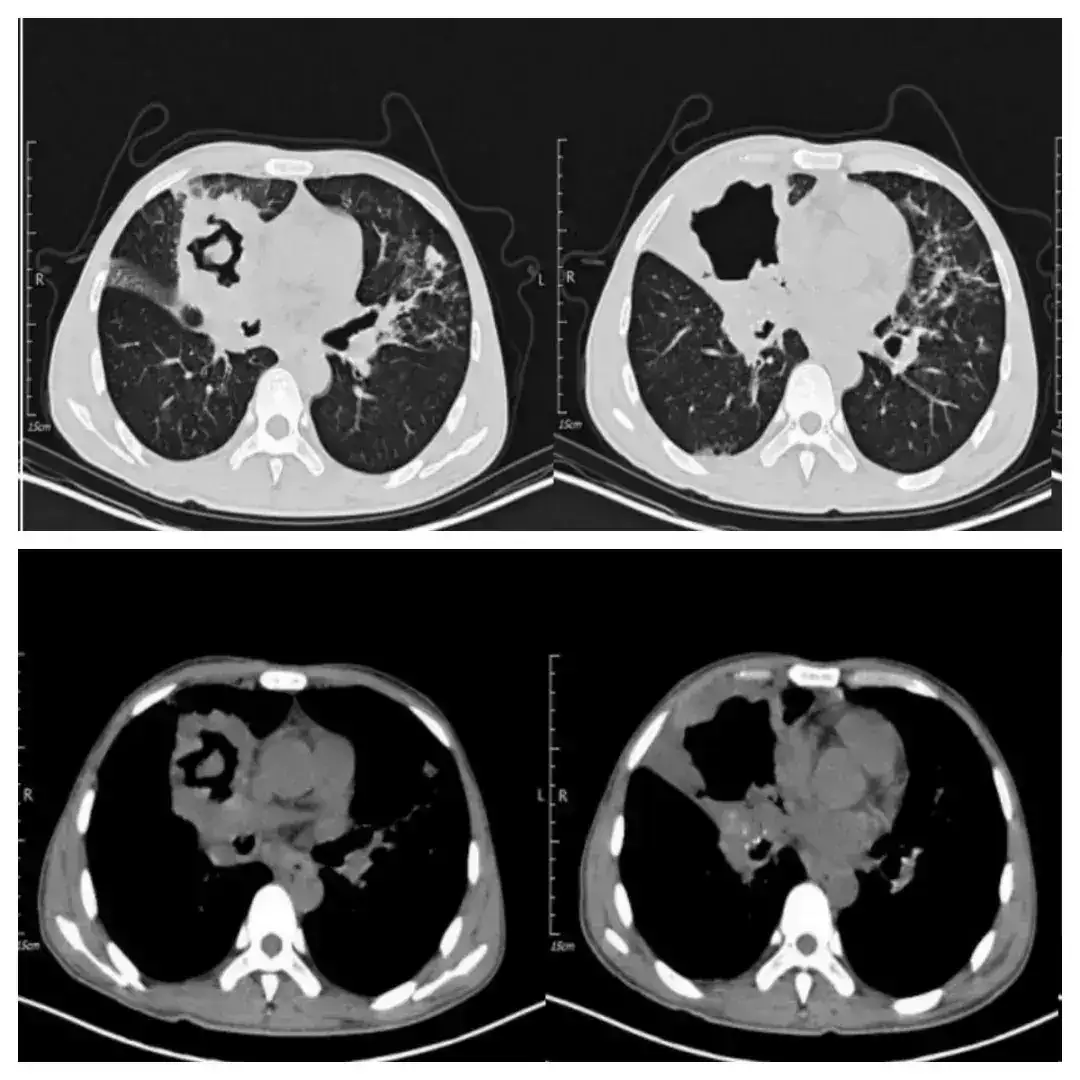

解放军总医院呼吸学部赵凡杰医生介绍病例:“患者男性,40岁,以反复发热、咳嗽、咳痰2月余,咯血1天来诊。患者院外抗感染等药物治疗效果不佳,胸部CT提示右肺占位、空洞形成,双肺炎症,电子支气管镜检查提示右肺中叶坏死物质堵塞管腔,灌洗液NGS提示:肺炎克雷伯菌,序列数2,低信号强度;人类疱疹病毒4型,序列数20,信号强度低;活检病理提示肿瘤性病变可能性大,结核不除外。最终病理诊断出乎意料,感染?肿瘤?还是另有其他,敬请关注谜底揭晓。”